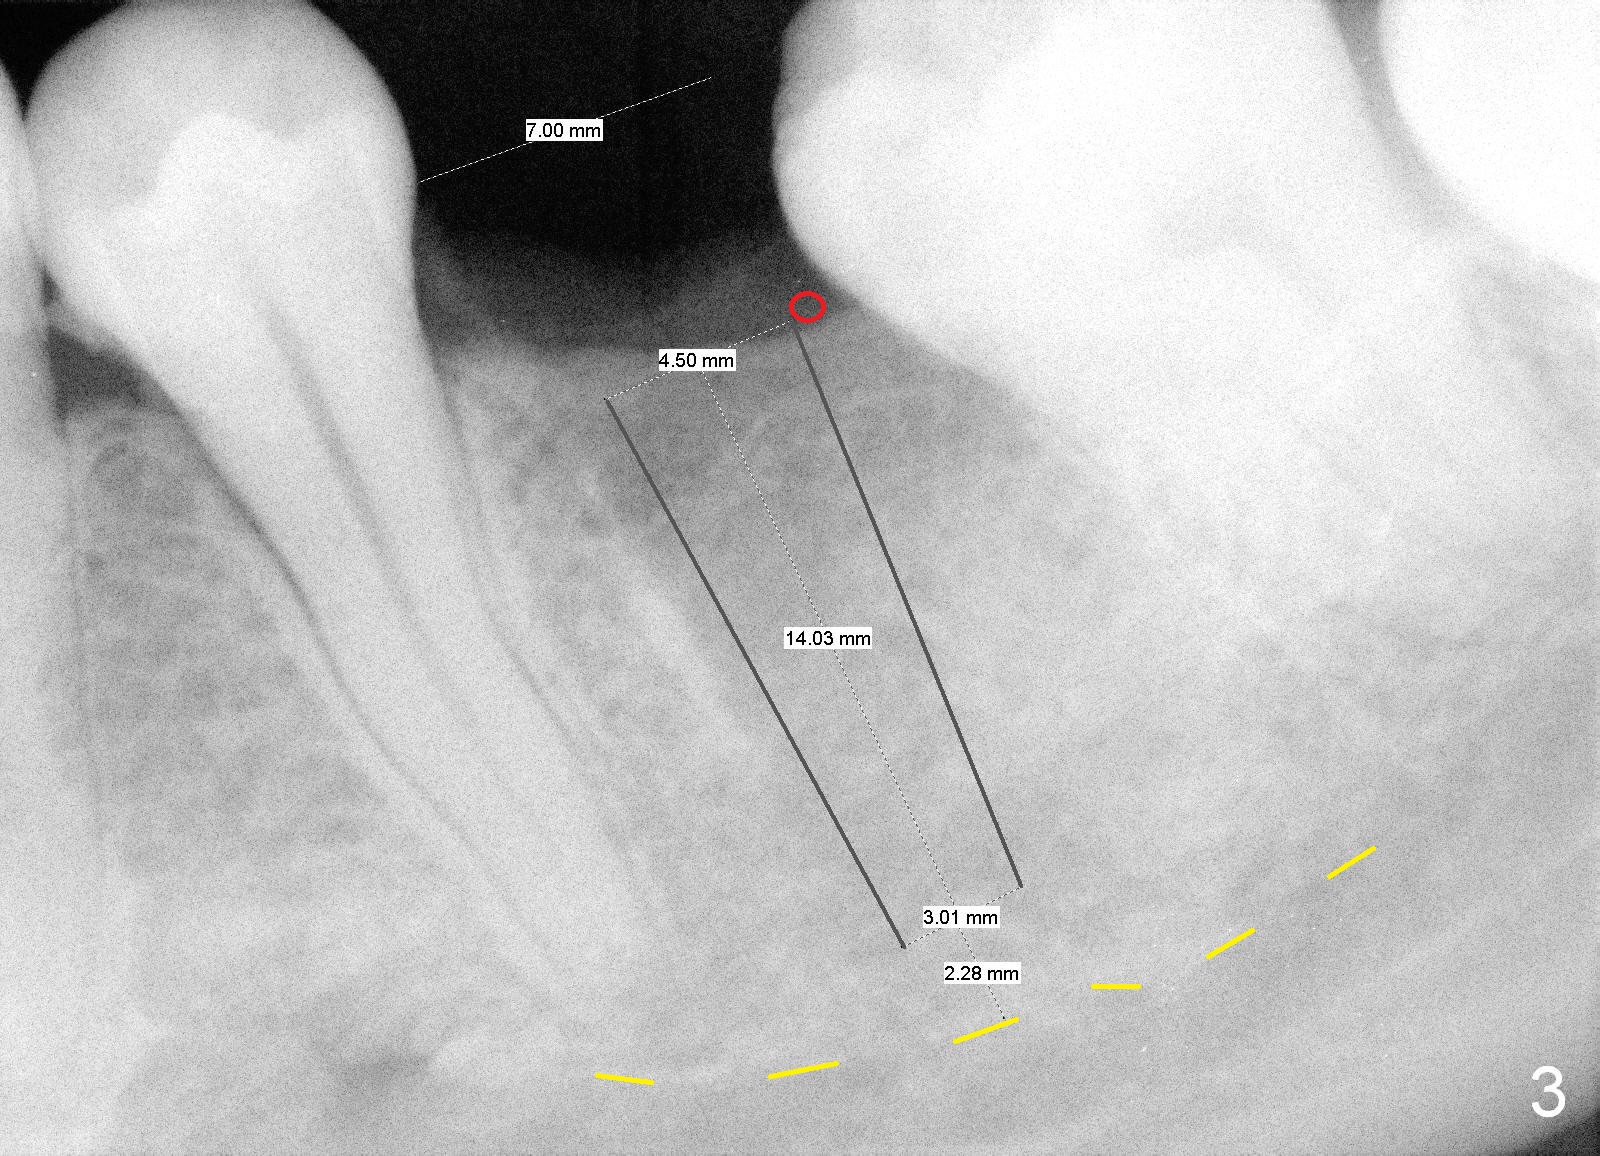

A 29-year-old man presented for #19 extraction a year ago (Fig.1). Probably due to long-termed loss of the distal portion of the crown of #19 (*), the tooth #18 has undergone mesial tilting (arrow). Now he returns requesting implant, but the tilting is worse (Fig.2 double arrows). What X-ray cannot show is severe atrophy buccolingually, increasing difficulty in implant placement. A much smaller implant can be placed (Fig.3), as compared to an immediate implant.